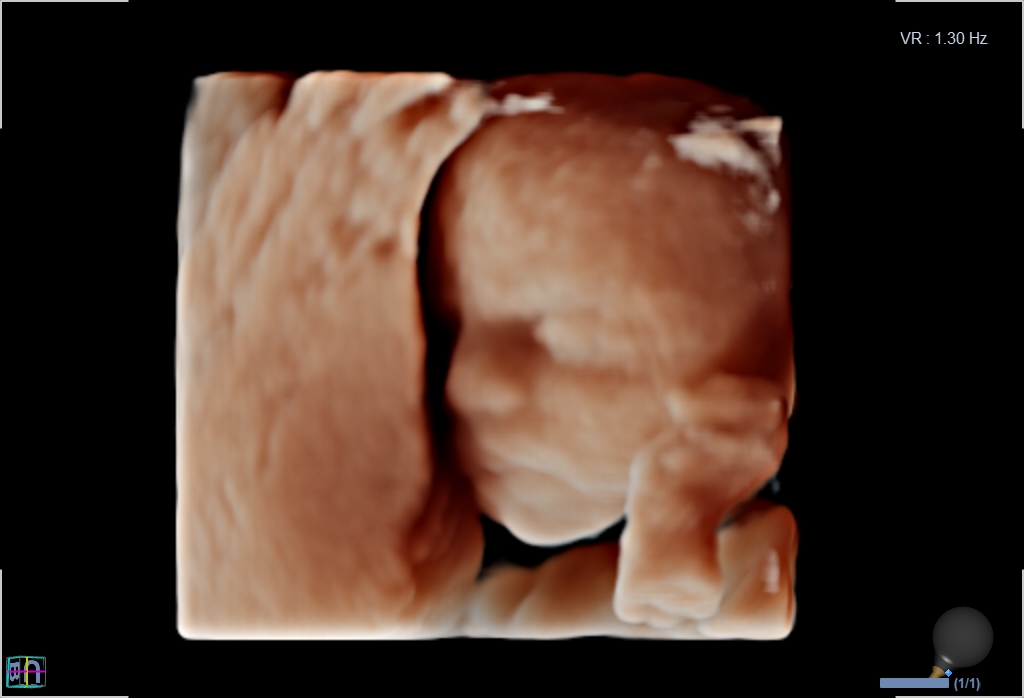

3D/4D-Ultraschall für Schwangere

Ergänzende Sonographie als Wahlleistung

Seit März 2019 steht ein neues 3D/4D-Ultraschallgerät für faszinierende Eindrücke von Ihrem Baby zur Verfügung.

Außer den Fotos können auch 3D/4D Viedeoclips gemacht und auf einem USB-Stick gespeichert werden. So können die Bilder und Clips jederzeit angesehen werden.